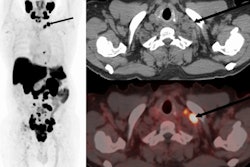

A 62-year-old patient with a history of prostate cancer initially treated with prostatectomy, prostate bed radiation therapy, and six months of androgen deprivation therapy (ADT), who presented with suspected recurrence (prostate-specific antigen [PSA] level of 5.7 ng/mL). F-18 PSMA-1007 PET/CT detected pelvic lymph nodes (red arrow) and bone metastases (green arrow) that were not detected by F-18 fluorocholine PET/CT. Therapeutic management changed from targeted radiation therapy before PET to ADT after PET, leading to drop in PSA level to 0.1 ng/mL at six months. Image and caption courtesy of the Journal of Nuclear Medicine through CC BY 4.0.According to the analysis, the overall proportion of patients with correct detection rates for prostate cancer lesions with F-18 PSMA-1007 was 82% compared with 65% for F-18 FCH-PET. When the readers considered initially undetermined results as positive for malignancy, F-18 PSMA-1007 PET/CT helped identify 77% of cases compared with 57% for F-18 FCH-PET/CT, the group wrote.